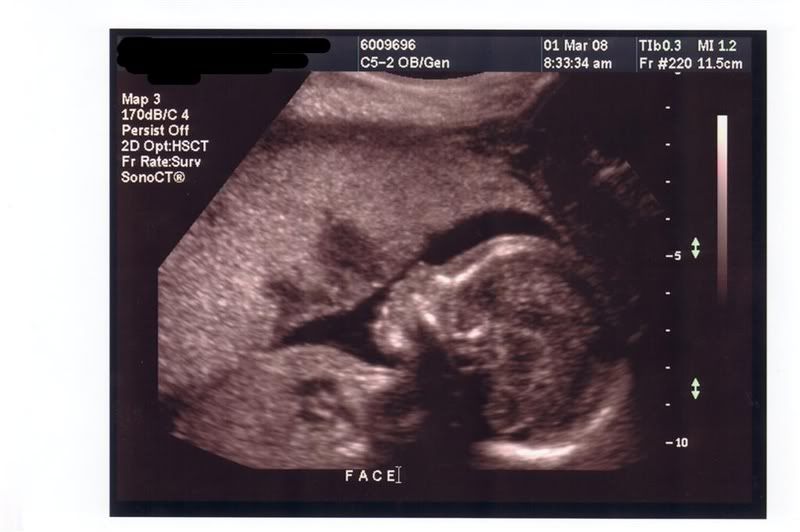

Ultrasound Pictures

We had our appointment today, we are relieved that not only is the baby okay; but there is only one... They got us in right away but me and my son had to wait outside for awhile until they had finished. Then they copied everything to CD for us, which I really appreciate.

So heres our new baby at 9 weeks: